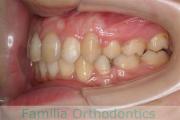

No.23V-478

- 主な症状:

- 叢生

- 年齢:

- 30歳

- 性別:

- 男性

- 抜歯部位

- 上:

- 44済

- 下:

- 8558済

- 主な使用装置:

- FEA 022

- 治療にかかった費用:

- 76万円

右上の歯が重なっているところが邪魔になるとのことで矯正治療を始められた患者さんで、札幌から転院されました。当院で約1年半、15回程度の通院が必要でした。叢生(でこぼこ、凹凸、ガタガタ)が強く、後戻りのリスクが高いケースです。